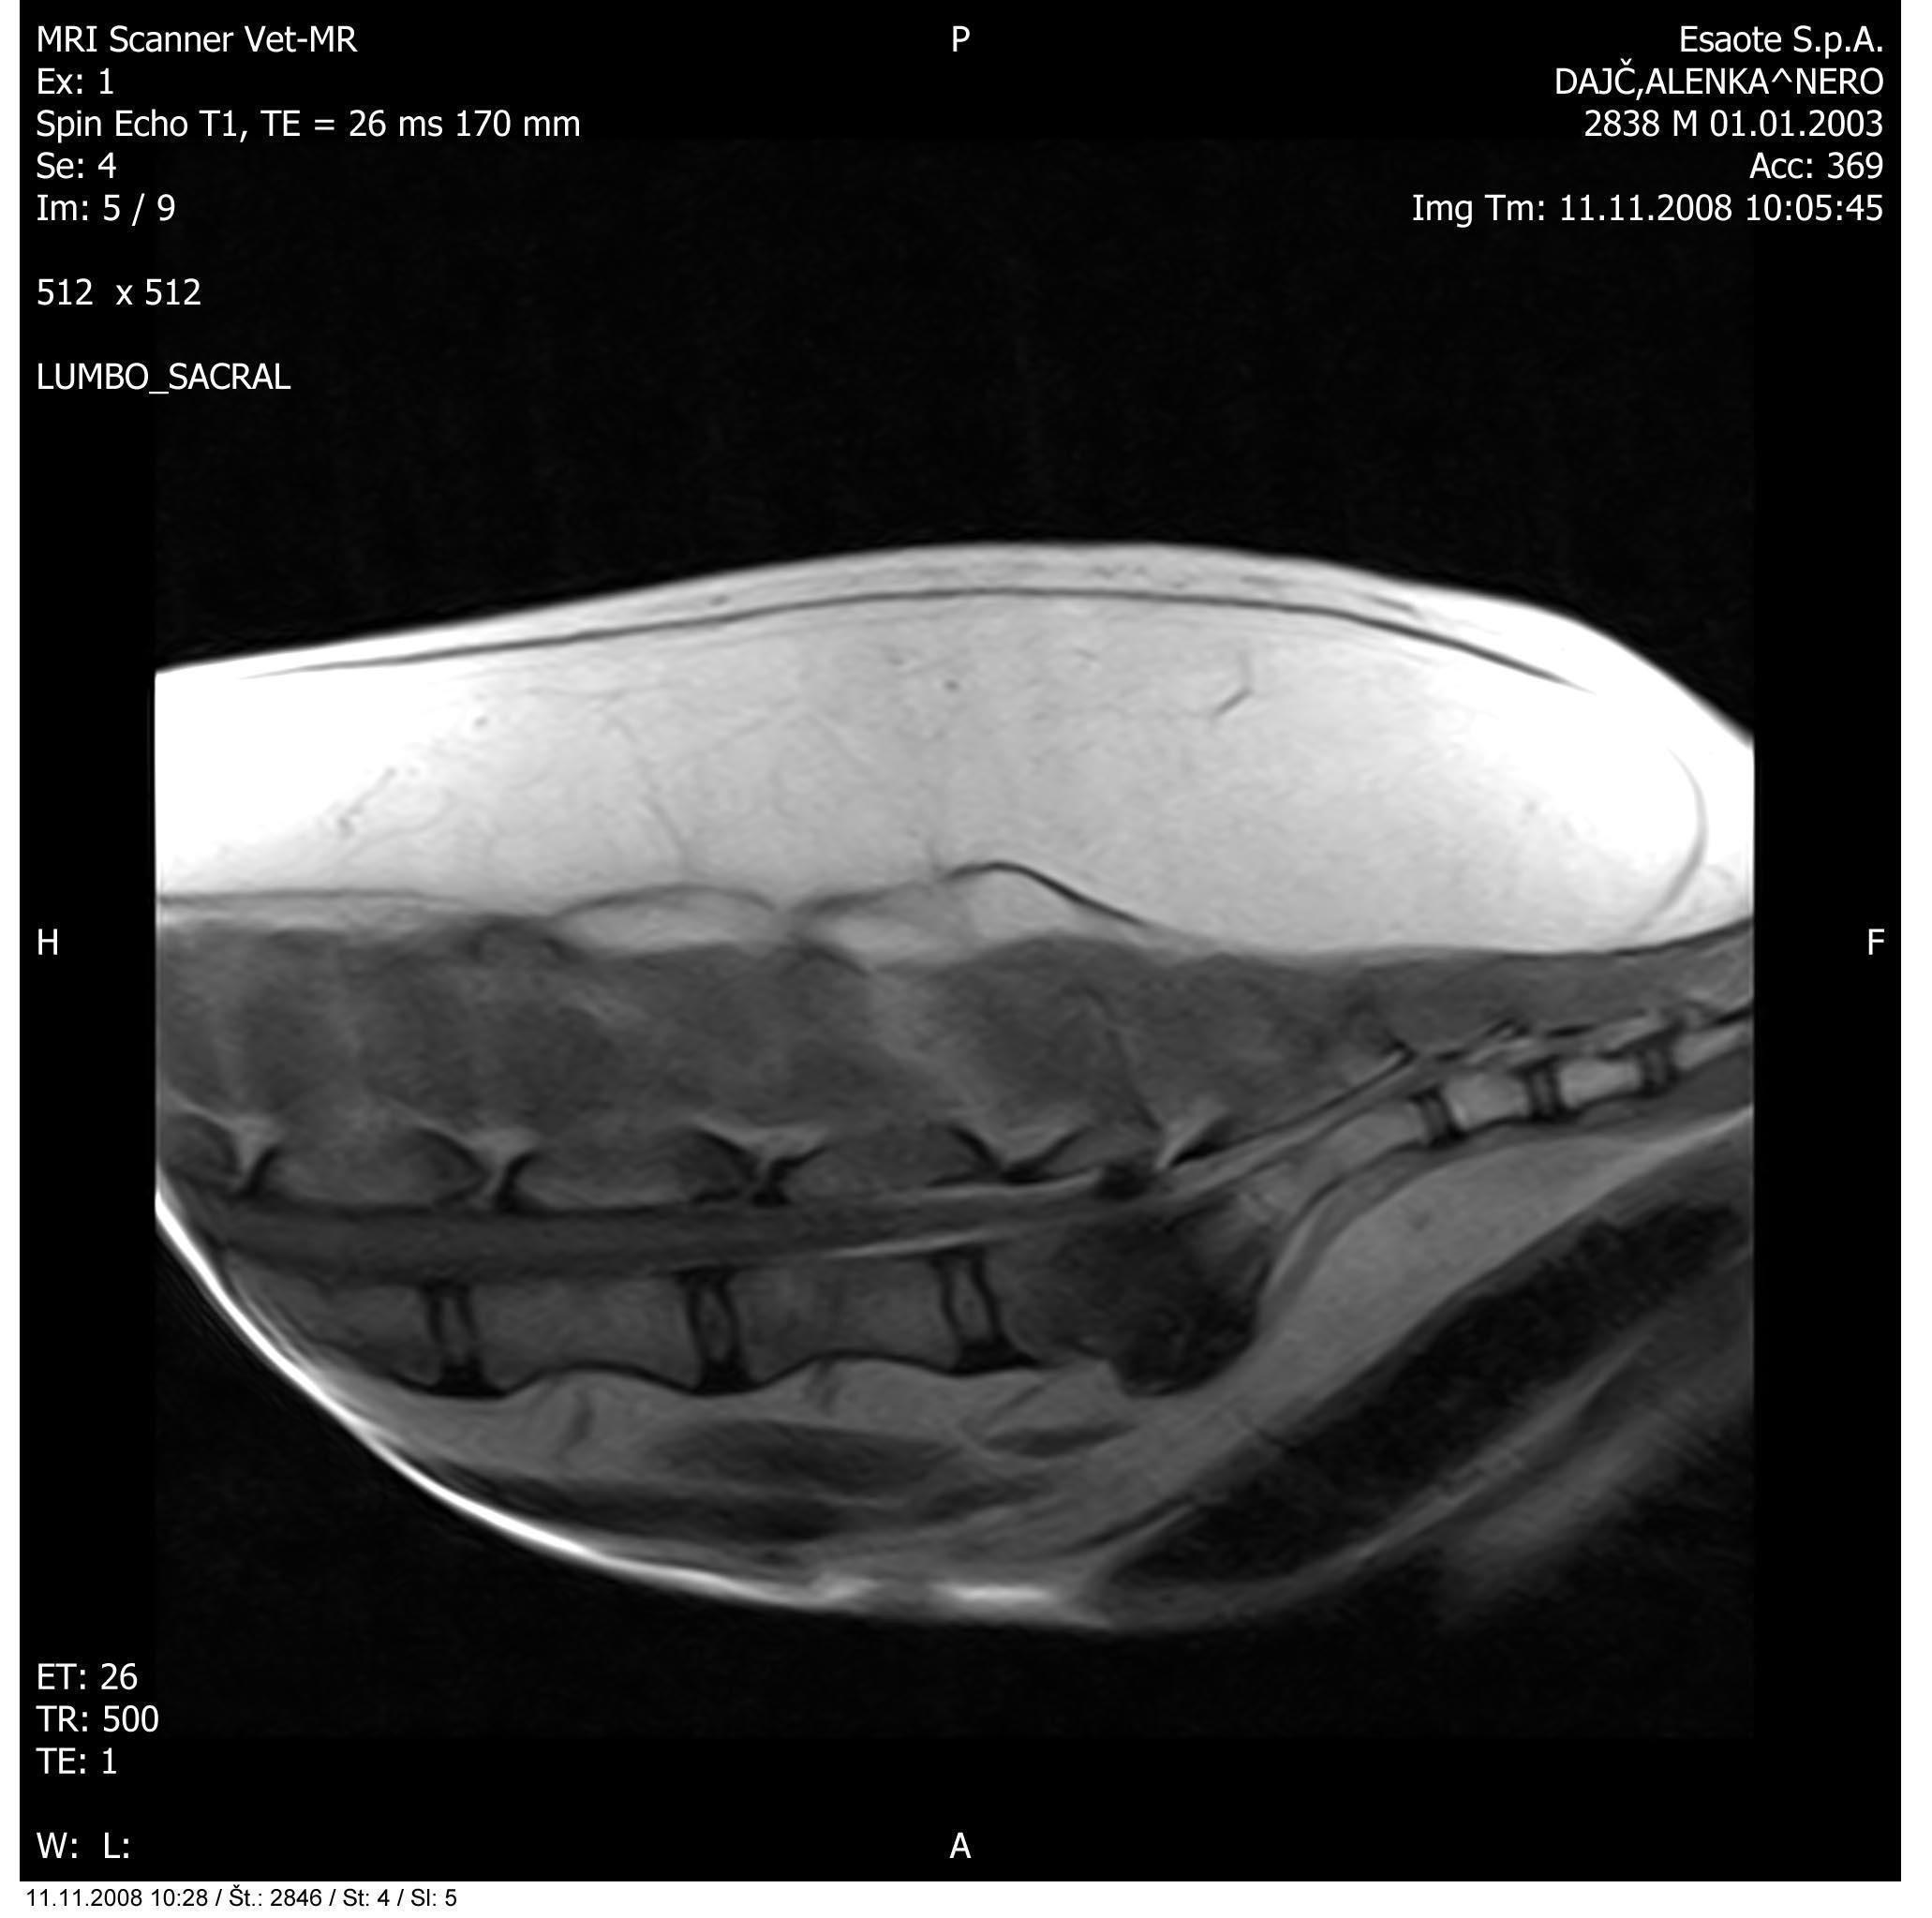

Slika: Primer vnetega medvretenčnega diska

Magnetna resonanca je torej diagnostična metoda izbora pri ugotavljanju patoloških dogajanj v mehkih tkivih glave in hrbtenice. O leziji pri MR govorimo o vsakem področju, kjer je signal drugačen kot običajno. Na podlagi ocene slik v vseh treh ravninah natančno določimo lokacijo, obseg in vpliv spremenjenih tkiv na okolna tkiva.

Zanima nas število lezij, njihova oblika, robovi, vraščenost, ugotavljamo prirojene ali pridobljene anomalije (na primer hidrocefalus, siringomielija in drugo), potrdimo tipe lezij: degenerativne (na primer starostna atrofija, degenerativna mielopatija, bolezni medvretenčnih diskov in drugo), tumorozne (na primer meningiomi, gliomi, metastaze in drugo), vnetne (na primer meningoencefalitis, diskospondilitis in drugo), žilne (infarkti, poškodbe, embolija diska in drugo) ter druge.